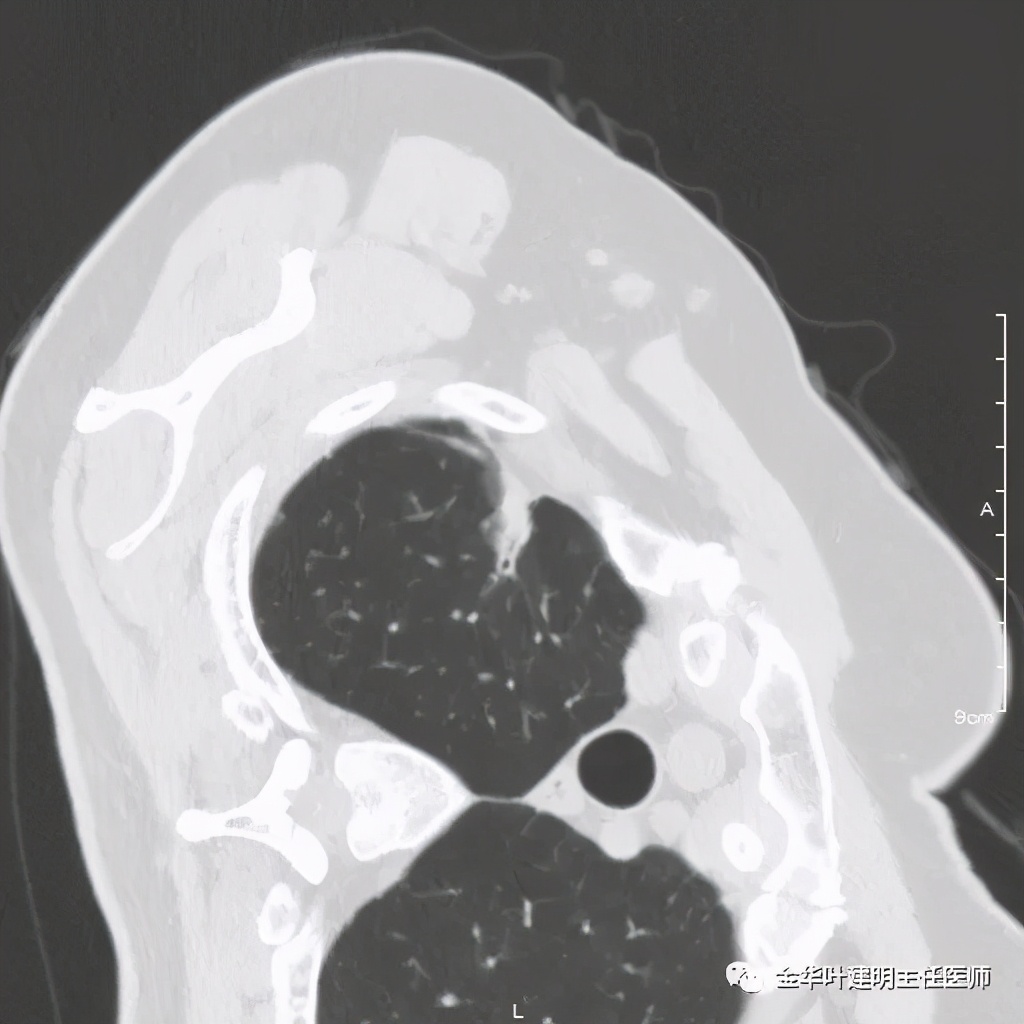

六、神经内分泌癌(此例为不典型类癌,小细胞癌以后再总结):

影像特征:不典型类癌一般圆形生长,实性,边缘比较光滑,但硬度不够。侵蚀力也不够。就像这例,我们发现其与肺动脉接触的地方,居然无法推压血管,反而肿瘤被血管占据了其生长的位置,在支气管内,肿瘤也是对支气管壁没有造成明显的破坏。也就是说 圆形边清较软、侵蚀力弱的实性结节 要考虑类癌的可能性。